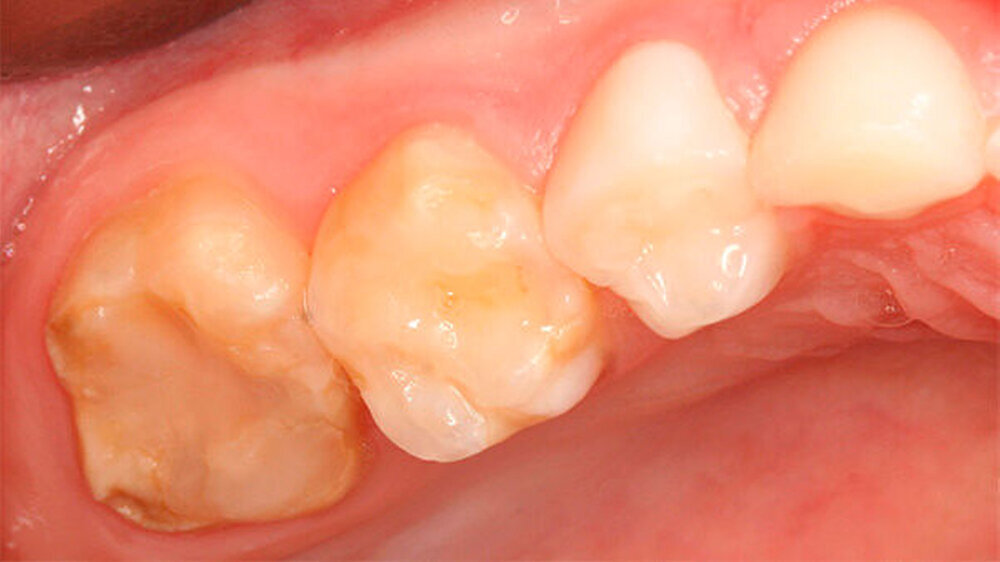

Zahn 26, auf den laut Hauszahnarzt ein besonderer Fokus gelegt werden sollte, stellte sich wie folgt dar: Klinisch waren etwa zwei Drittel des Zahnes restaurativ versorgt. Die noch bestehenden Höcker im mesio-bukkalen und disto-palatinalen Bereich, die unmittelbar an die adhäsiv befestigte Abdeckung grenzten, wiesen weitere Opazitäten auf (Abbildung 2).

Zudem war - wenn auch gering ausgeprägt - eine Opazität im mesio-palatinalen Anteil des zweiten Milchmolaren zu erkennen, sowie sehr schwach ausgepägt im mesio-bukkalen Anteil des gleichen Zahns (Abbildung 2).